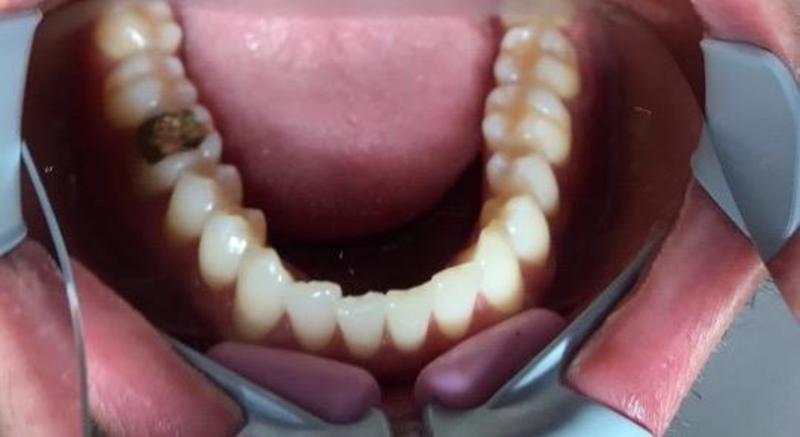

1. Photos du patient avant le traitement

Le patient souhaitait une correction dentaire ; il se plaignait principalement d'un encombrement antérieur dans les deux mâchoires.

Léger encombrement antérieur sur les deux arcades

Rotations des dents 22, 31, 32, 41, 42, position d'inclinaison palatine des dents 11, 21